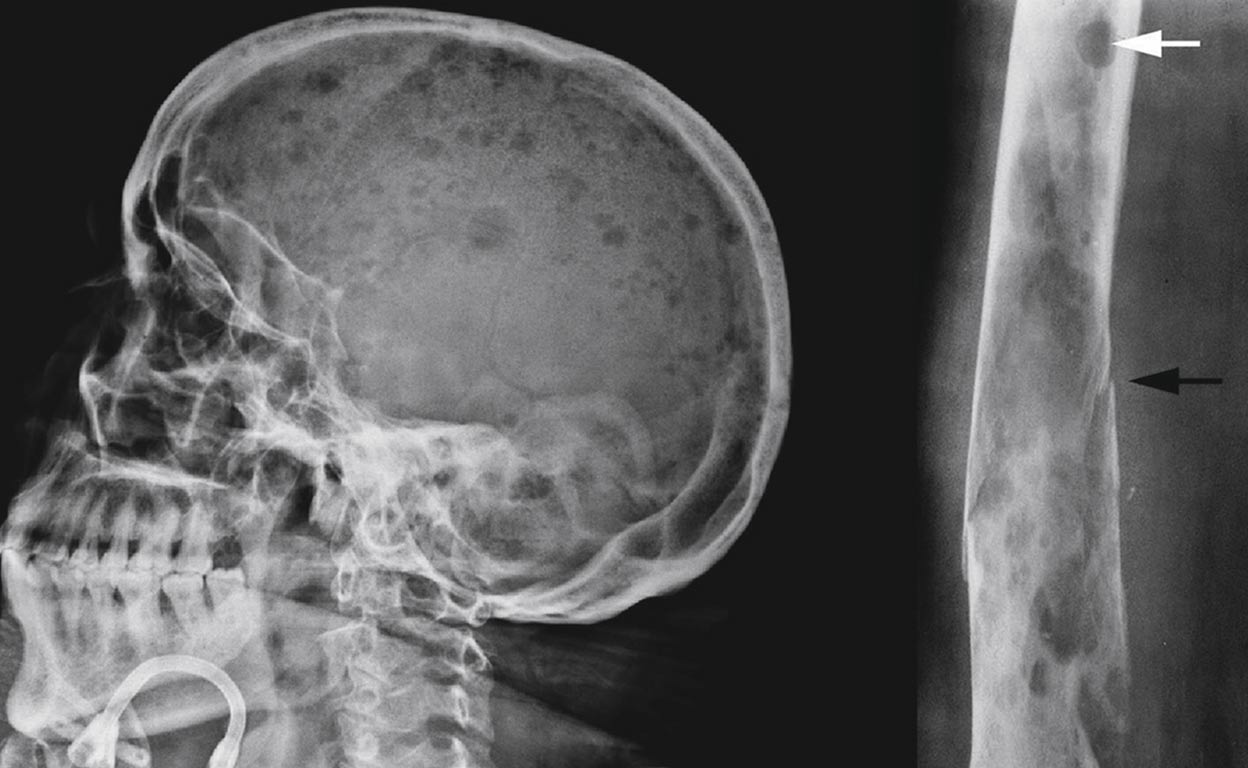

El mieloma múltiple (MM) es un tipo de cáncer que afecta las células plasmáticas en la médula ósea, comprometiendo el sistema inmunológico y provocando complicaciones graves como anemia, problemas renales, lesiones óseas e infecciones recurrentes. Según datos de Globocan 2022, en México se registraron 2,346 nuevos casos de esta enfermedad, con una prevalencia de 7,026 personas viviendo con MM.

Además, 1,507 personas fallecieron a causa de esta enfermedad, representando el 10% de las muertes por neoplasias hematológicas.